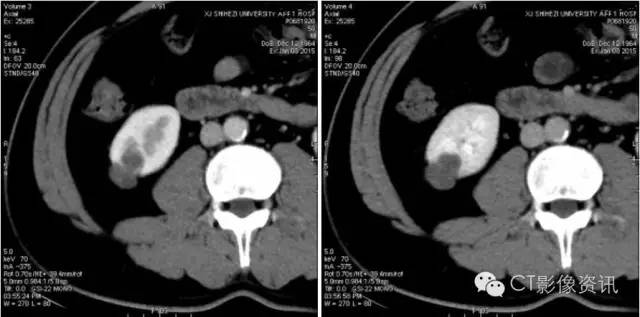

三期冠状位测量结果显示同样结果。肝实质、肾脏髓质均有明显强化。

最终诊断:肾囊肿。

讨论 能谱的功能可以解决临床中有争论或者诊断不明确的情况。尽管常规显示中似乎有强化的存在,但不能确切诊断。但该病例通过碘含量的测量,明确了病灶没有强化。为最终诊断定下根本的线索。